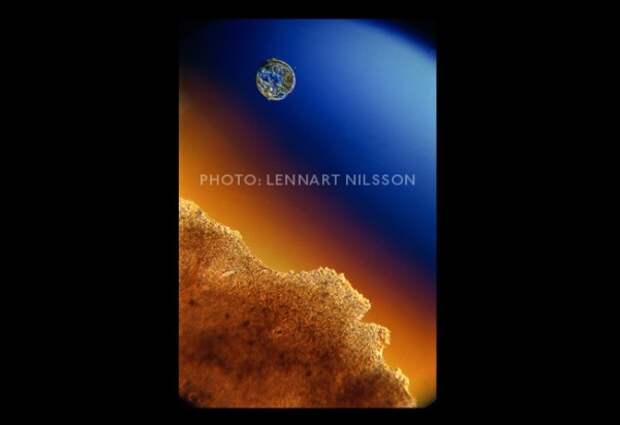

Фактрум предлагает вашему вниманию работы фотографа Леннарта Нельсона. Нельсон прославился на весь мир благодаря своей фотокниге под «A Child is Born», увидевшей мир в 1965 году. Ему удалось заснять развитие эмбриона удалось при помощи цистоскопа — медицинского прибора, которым осматривают мочевой пузырь изнутри.